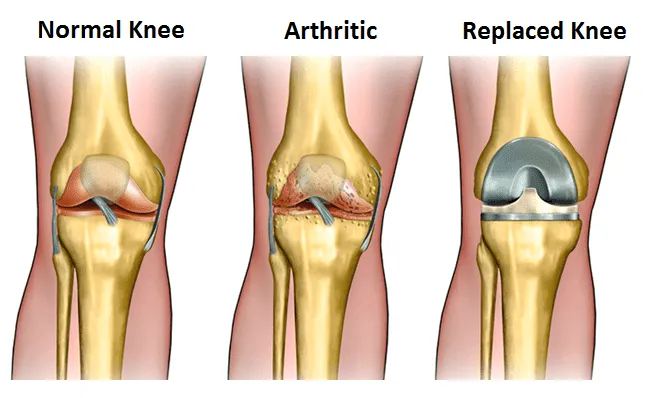

When it is healthy, the knee is a remarkable mechanism. In a healthy knee, a layer of cartilage covers the surface of the joint allowing smooth motion.

When arthritis intrudes; however, the protective layer of cartilage in the knee gradually wears away, becoming frayed and rough, making it painful to move the joint. The knee then becomes unable to effectively cushion the body from impact and stress. The result is a painful joint that can gradually hamper your quality of life, reduce your independence, and make it hard – or impossible – to do the things you want to do.

Total Knee Replacement is the surgical removal of the damaged joint and replacing it with an artificial joint that is attached to the thigh bone (femur) and the shinbone (tibia).

Knee replacement is recommended when the knee joint and cartilage is too worn out damaged due to any of the above-mentioned causes.

Without the replacement, the pain is going to be persistent and can lead to deformity of the knee. This can also put your body of a higher risk of strain on other body parts and joints.

We remove the damaged cartilage and bone from the knee to replace with metal and plastic molded implants. The new implants make the joint movements smooth enabling them to work freely and relieving you of the pain caused earlier.